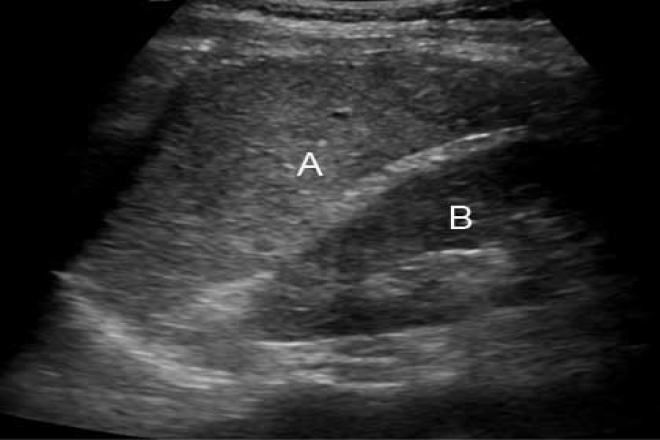

Mujer de 30 años, sin antecedentes de interés, que se realiza un USG ginecológica de rutina es diagnosticada de masa pélvica. Se completa estudio con una TAC, en donde se observa un bazo errante visualizando el pedículo vascular que desciende desde hipocondrio izquierdo.

Se realiza TAC abdominal con medio de contraste en el que se aprecia esplenomegalia con ausencia de captación del medio de contraste y una imagen en con disposición espiral a nivel del hilio esplénico, que hacen sospechar de una torsión esplénica.

El USG y TAC son medios no invasivos de gran utilidad que nos dan un diagnostico rápido ya que el primero nos informa sobre su grado de ecogenicidad del bazo y el segundo observamos alguna torsión o infarto, y permite demostrar una disposición de los vasos del hilio por medio del medio de contraste.